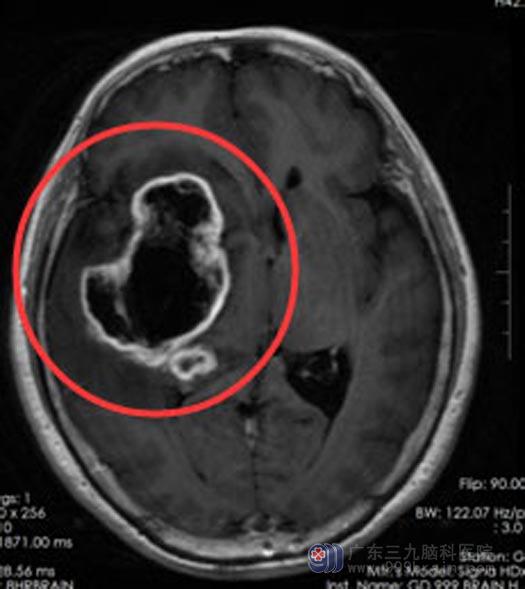

这次是在骑车买菜回家的路上,突然记忆混乱,想不起来回家的路,万幸的是可以迷迷糊糊地记得家里的电话号码,从断断续续的回答里,家人总算费劲地找到了她,当时的周阿姨已经连走路都不稳了。立即在当地医院头颅MR检查,提示:右额颞叶异常信号,考虑低级别胶质瘤。

得知是恶性肿瘤,家人连夜带着周阿姨赶到广东三九脑科医院。进一步MR灌注+DTI+MR检查结果:ASL检查示右额颞顶基底节区病灶异常环形高灌注。

周阿姨和家属都同意手术治疗。由综合神经外科鲁明副院长主刀在唤醒麻醉下行“右额颞顶基底节占位切除术+硬脑膜修补术+颅骨成形术”。导航定位右额颞顶基底节区肿瘤组织,术中唤醒患者,电生理监测运动中枢,结合导航,避开上下肢运动区,显微镜下将肿瘤分块切除,手术非常顺利。